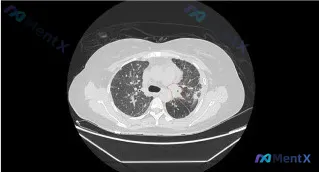

整理了一个有意思的病例,核心是ALK-TKI靶向治疗11个月后CT提示进展,影像表现和病史结合起来有几个容易踩坑的点,分享一下我的分析思路。 --- 一、先把核心信息摆出来 1. 背景病史:ALK阳性肺癌,使用ALK-TKI治疗11个月 2. 本次影像(胸部CT肺窗): - 主要病灶:左肺上叶,混合...